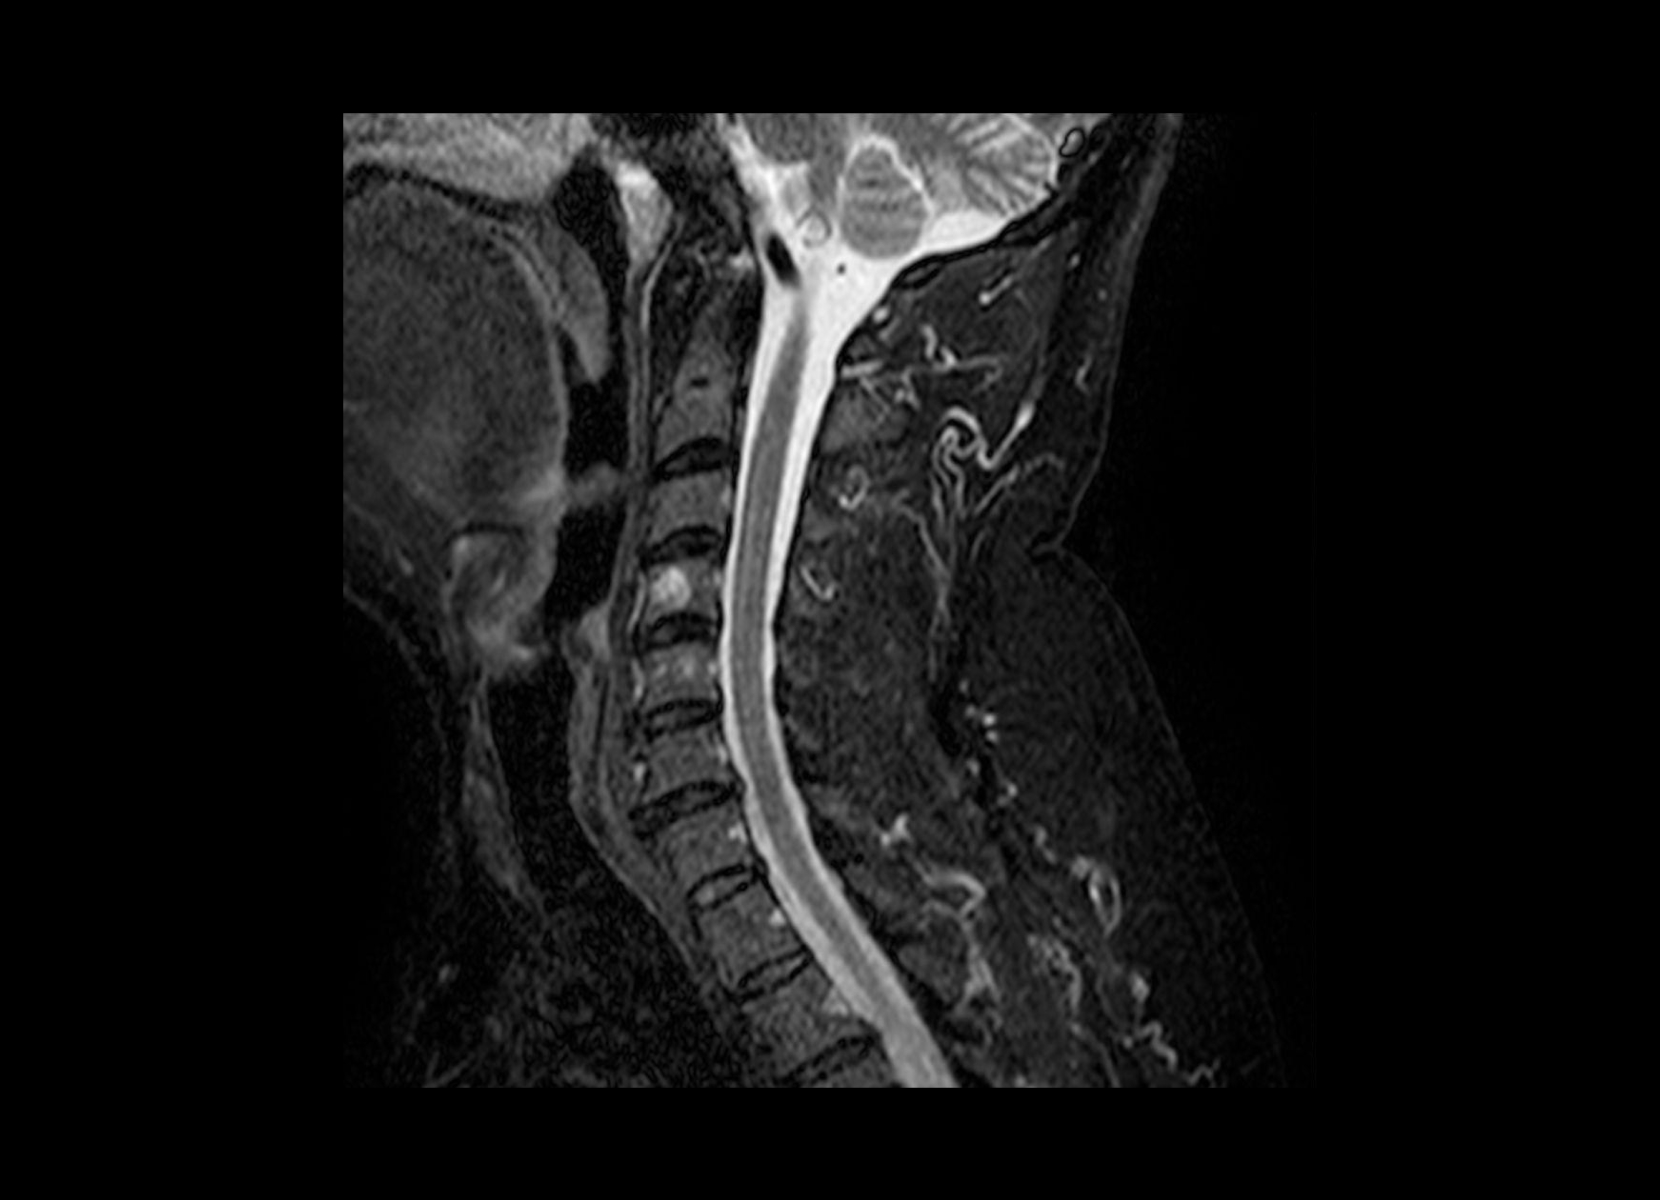

Conventional

STIR

SubtleSYNTH™

(Synthesized STIR)™

Trauma

GE 1.5T

C-spine